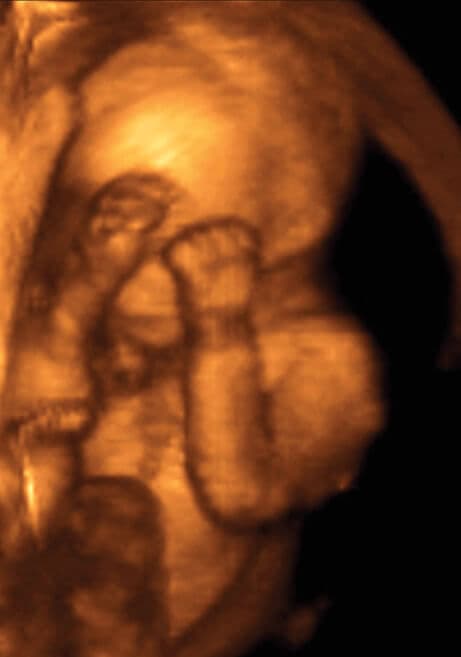

19 weeks and 6 days pregnant

You will become much more aware of your baby moving as her size and strength increase. You will not be aware of the more gentle movements, or those movements that do not hit the side of the uterus.